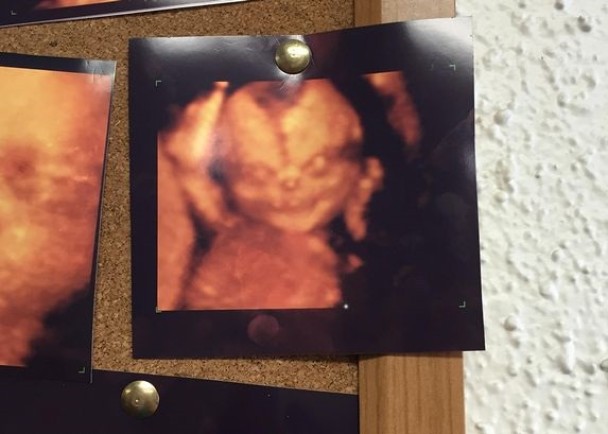

4D超声波照惊现恐怖胎儿照 英国夫妇吓出冷汗 来源: 神秘的地球 时间:2015年8月17日 15:28 这张恐怖4D超声波照在网上疯传 (神秘的地球报道)不少夫妇现时都会为胎儿照4D超声波,但英国一对准父母见到这张超恐怖BB照后,立即改变主意,只照普遍超声波。 社交网Reddit一名相信是准爸爸的用户,称日前与怀孕妻子到诊所,本希望为胎儿照4D超声波,但在诊所看到多张超声波照中,其中一张貌似恶魔般奇异的胎儿照,背部不禁冒出冷汗,两人随即打退堂鼓。他上载该照片后,网民迅即疯传,直言令人感不安。 上一篇 下一篇 TAG: 英国